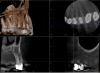

Fig 14. Preoperative radiographic image (Fig 14), preoperative CBCT (Fig 15), postoperative scans (Fig 16 and Fig 17), and inverted postoperative image (Fig 18).

Figure 14

Fig 15. Preoperative radiographic image (Fig 14), preoperative CBCT (Fig 15), postoperative scans (Fig 16 and Fig 17), and inverted postoperative image (Fig 18).

Figure 15

Fig 16. Preoperative radiographic image (Fig 14), preoperative CBCT (Fig 15), postoperative scans (Fig 16 and Fig 17), and inverted postoperative image (Fig 18).

Figure 16

Fig 17. Preoperative radiographic image (Fig 14), preoperative CBCT (Fig 15), postoperative scans (Fig 16 and Fig 17), and inverted postoperative image (Fig 18).

Figure 17

Fig 18. Preoperative radiographic image (Fig 14), preoperative CBCT (Fig 15), postoperative scans (Fig 16 and Fig 17), and inverted postoperative image (Fig 18).

Figure 18

Figure 14 and Figure 15 show the preoperative digital images for another case with a necrotic pulp. In the preoperative 3D CBCT volume, the clinician observed that the mesiobuccal system, distobuccal system, and palatal system all communicated. On evaluating the mesiobuccal system, the clinician observed anastomoses between the canals. The clinician sought to employ a conservative approach to treating the case. Figure 16 and Figure 17 show the postoperative scans wherein it can be seen that the clinician practiced "directed dentin conservation" (a term attributed to Dr. David Clark and Dr. John Khademi and perpetuated by Dr. Eric Herbranson).12 The only mechanical objective not illustrated by this case is the continuous tapering preparation. Overall, the original root canal system anatomy was maintained and the foramen was kept as small as practical. Figure 18 shows an inverted postoperative radiograph that better illustrates both of these principles.